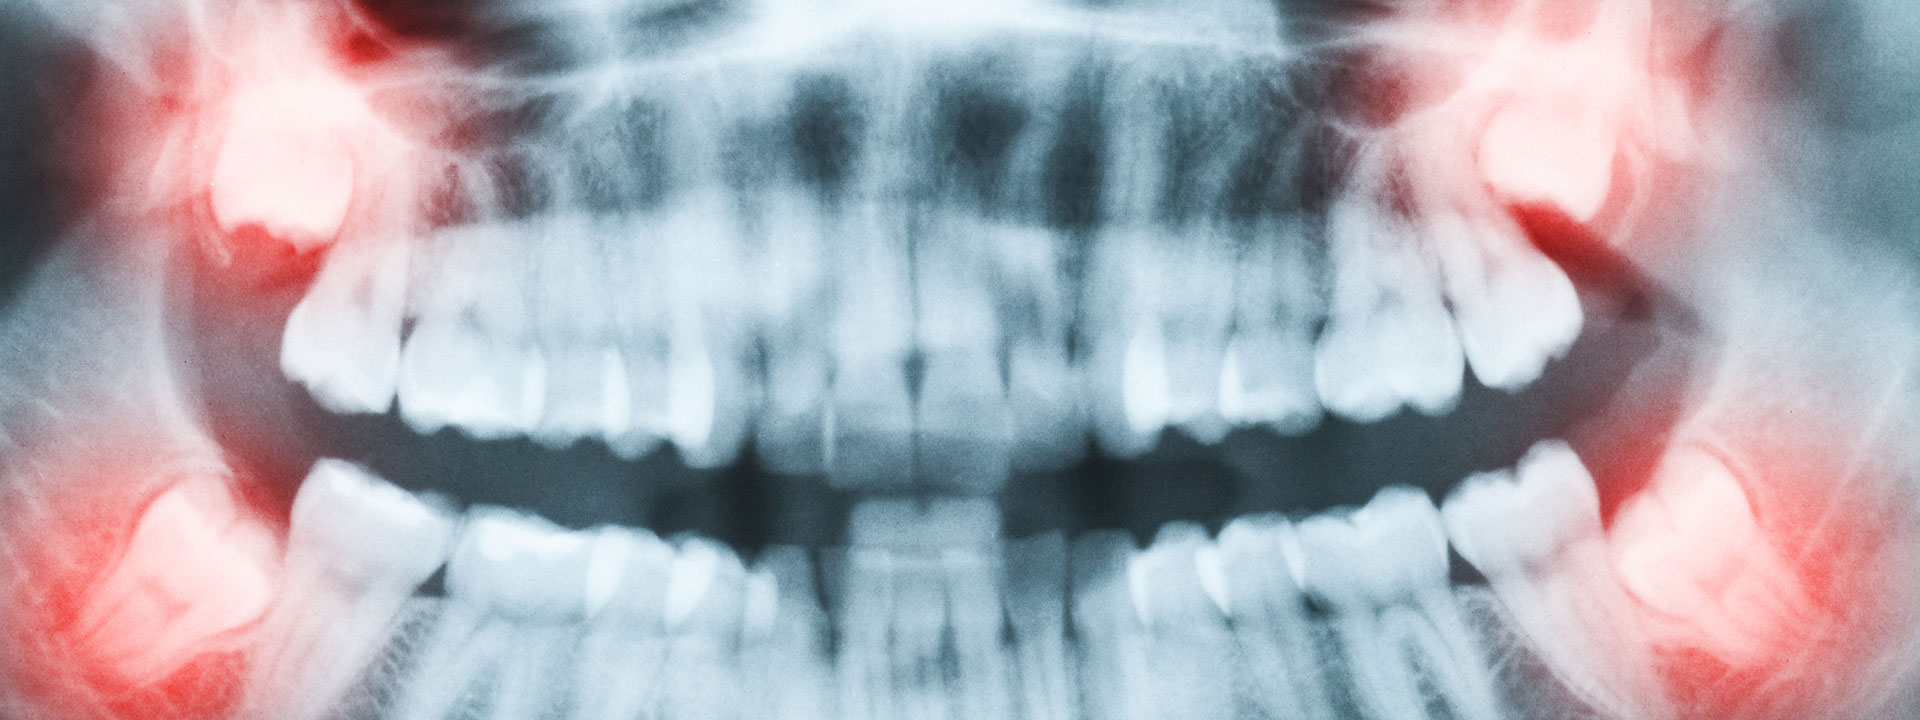

wisdom teeth xray

Wisdom Teeth Extraction

Wisdom teeth are the last teeth to erupt within the mouth. When they align properly and gum tissue is healthy, wisdom teeth do not have to be removed. Unfortunately, this does not generally happen. The extraction of wisdom teeth is necessary when they are prevented from properly erupting within the mouth. They may grow sideways, partially emerge from the gum, and even remain trapped beneath the gum and bone. Impacted teeth can take many positions in the bone as they attempt to find a pathway that will allow them to successfully erupt.

These poorly positioned impacted teeth can cause many problems. When they are partially erupted, the opening around the teeth allows bacteria to grow and will eventually cause an infection. The result is swelling, stiffness, pain, and illness. The pressure from the erupting wisdom teeth may move other teeth and disrupt the orthodontic or natural alignment of teeth. The most serious problem occurs when tumors or cysts form around the impacted wisdom teeth, resulting in the destruction of the jawbone and healthy teeth. Removal of the offending impacted teeth usually resolves these problems. Early removal is recommended to avoid such future problems and to decrease the surgical risk involved with the procedure.